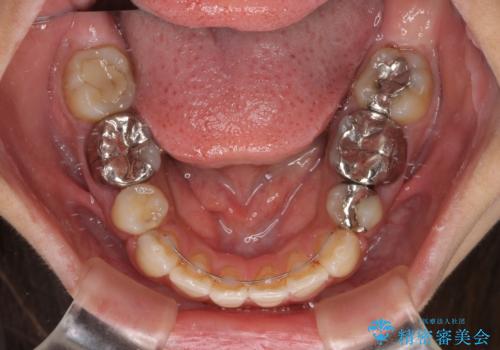

デコボコと口元の突出感 ハーフリンガルでの抜歯矯正

- 前歯のデコボコと上顎の前突感による口の閉じにくさを気にして来院された患者様です。

目立たない装置を希望されたので、上顎が裏側装置のハーフリンガルを選択し、上下左右の小臼歯(計4歯)を抜歯して矯正治療を行うこととしました。

表側のワイヤー矯正に比べると治療期間は長く、費用も高額となりますが、どうしても目立たせたくないという方にはお勧めの抜歯矯正です。